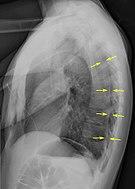

A large right-sided spontaneous pneumothorax (left in the image). An arrow indicates the edge of the collapsed lung

A plain chest radiograph, ideally with the X-ray beams being projected from the back (posteroanterior, or "PA"), and during maximal inspiration (holding one's breath), is the most appropriate first investigation.[25] It is not believed that routinely taking images during expiration would confer any benefit.[26] Still, they may be useful in the detection of a pneumothorax when clinical suspicion is high but yet an inspiratory radiograph appears normal.[27] Also, if the PA X-ray does not show a pneumothorax but there is a strong suspicion of one, lateral X-rays (with beams projecting from the side) may be performed, but this is not routine practice.[14][18]

The size of the pneumothorax (i.e. the volume of air in the pleural space) can be determined with a reasonable degree of accuracy by measuring the distance between the chest wall and the lung. This is relevant to treatment, as smaller pneumothoraces may be managed differently. An air rim of 2 cm means that the pneumothorax occupies about 50% of the hemithorax.[14] British professional guidelines have traditionally stated that the measurement should be performed at the level of the hilum (where blood vessels and airways enter the lung) with 2 cm as the cutoff,[14] while American guidelines state that the measurement should be done at the apex (top) of the lung with 3 cm differentiating between a "small" and a "large" pneumothorax.[28] The latter method may overestimate the size of a pneumothorax if it is located mainly at the apex, which is a common occurrence.[14] The various methods correlate poorly but are the best easily available ways of estimating pneumothorax size.[14][18] CT scanning (see below) can provide a more accurate determination of the size of the pneumothorax, but its routine use in this setting is not recommended.[28]